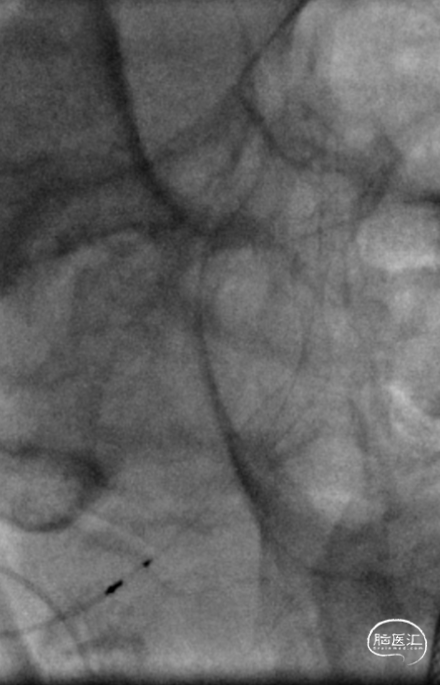

DSA示双侧椎动脉V4段狭窄,右侧为著且合并梭形动脉瘤。

术前DSA。

银蛇DA到位

Roadmap